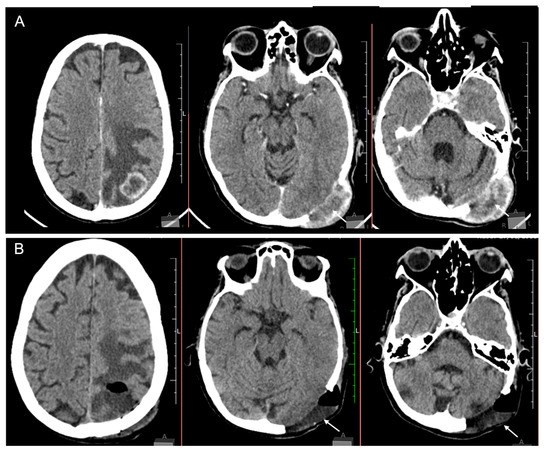

2. Case Report